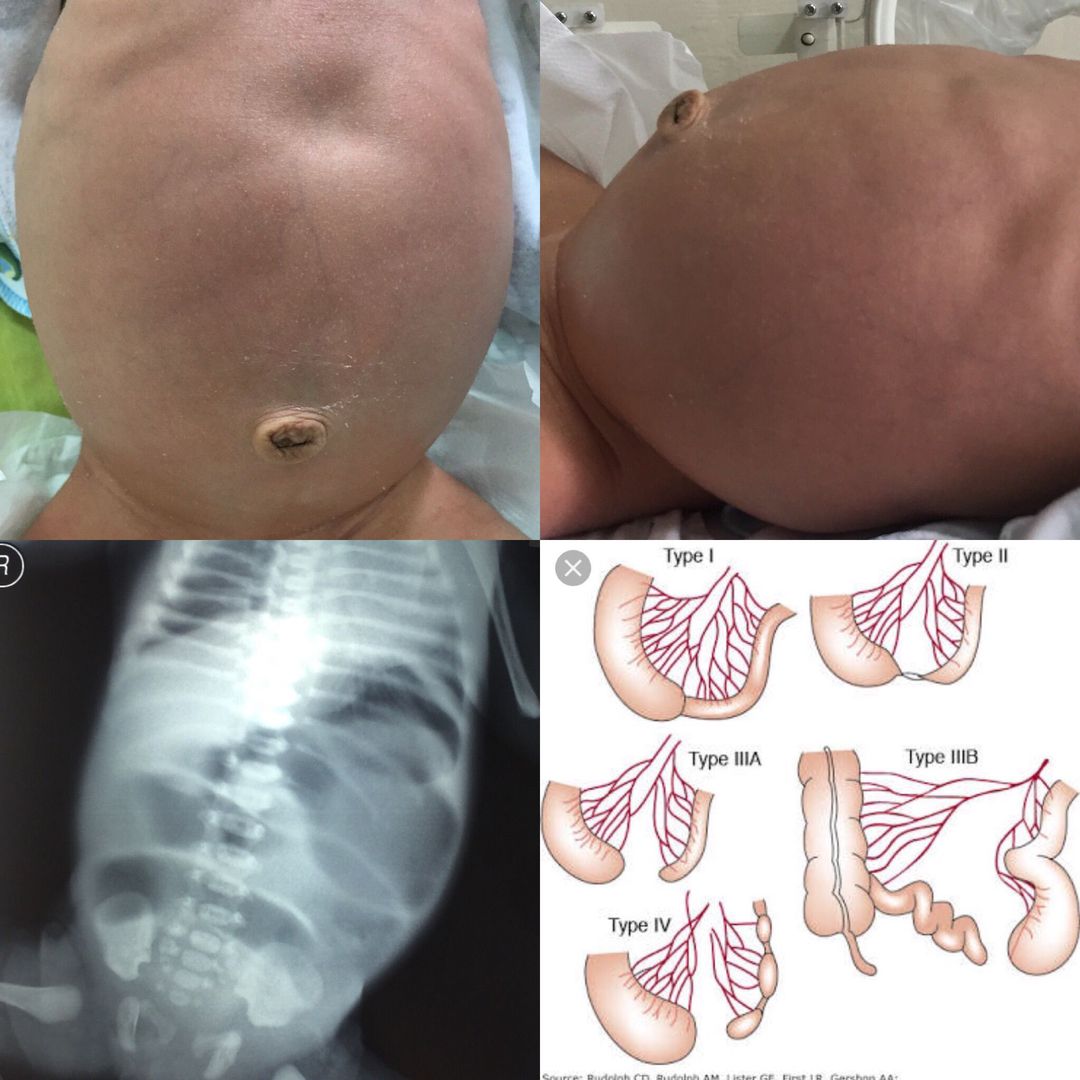

4 day-old full term baby boy presented with delayed passage of meconium (2 days), vomits 30-60 mins after milk consumption, abdominal distention. Picture: Bowel loops and peristalsis can be seen on abdominal surface. Plain abdomen xray shows multiple dilated small bowel loops and no air passage to the distal. Working diagnosis: Ileal atresia Differential diagnosis: Meconium ileus, long segment of Hirschsprung disease Operative finding: Type 1 ileal atresia